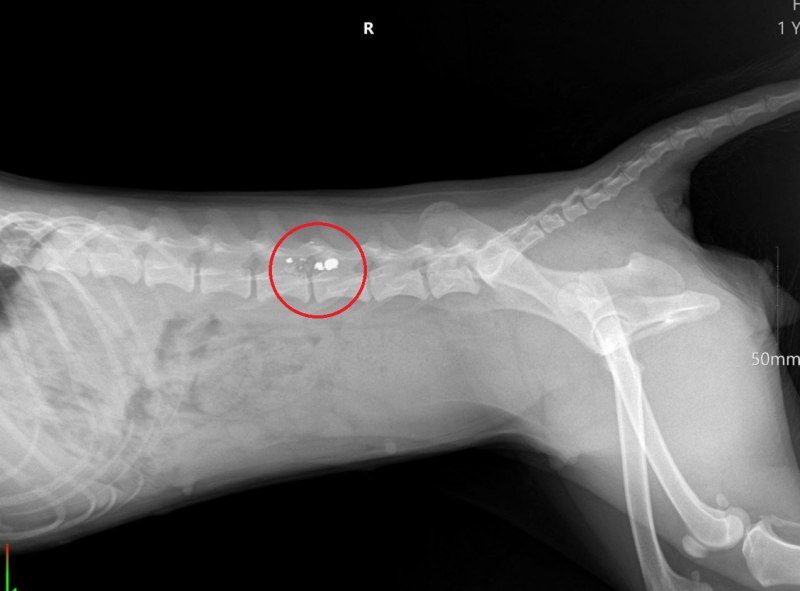

Хозяева доставили собаку в ветеринарную клинику. Врачи диагностировали травмы, которые привели к параличу тазовых конечностей.